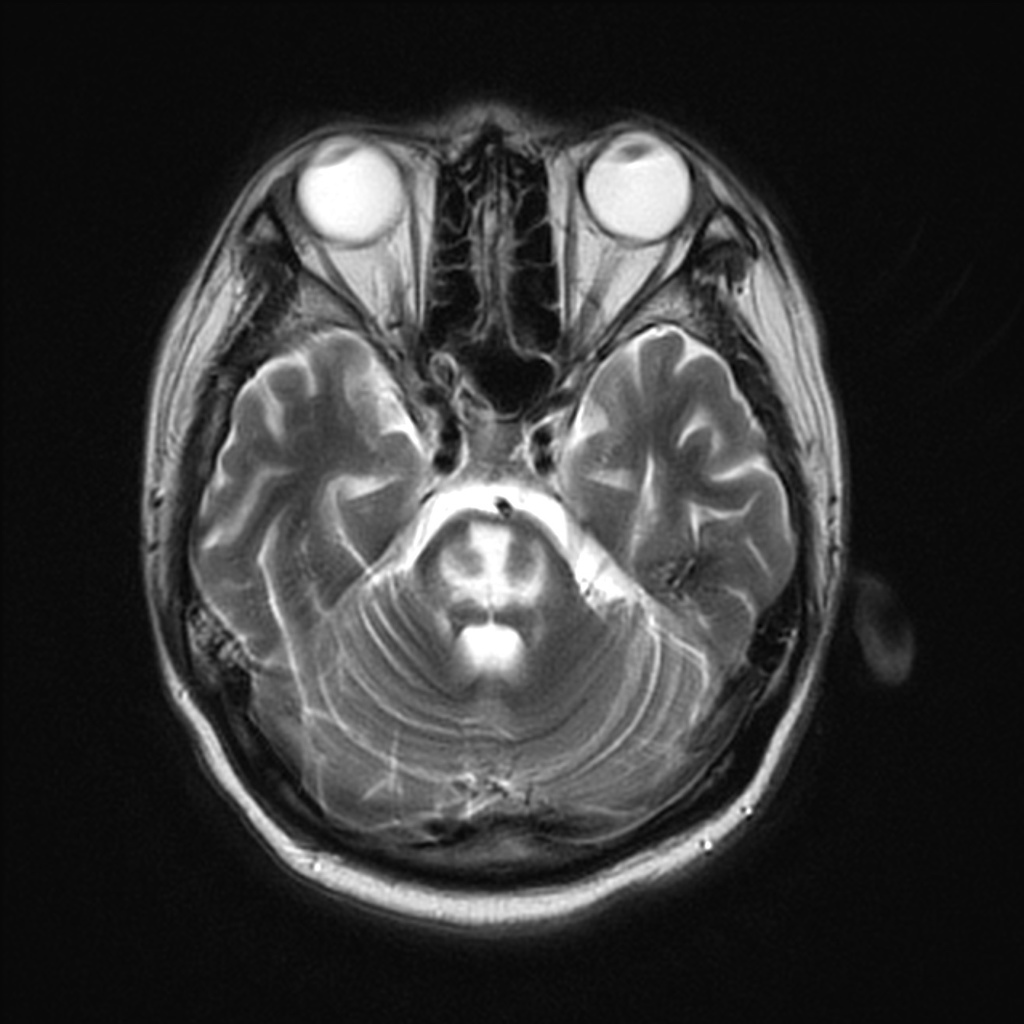

MRI T2/FLAIR on day 17

5 days later his conscious level reduced again and he developed spastic quadriplegia. An MRI scan later that day is shown above.

This is osmotic demyelination (old name: Central Pontine Myelinolysis) but it is a very unusual example caused by rapid onset of hypernatraemia. Usually it is attributed to too-rapid correction of very low plasma [Na], but presumably the principle is the same. A few principles.